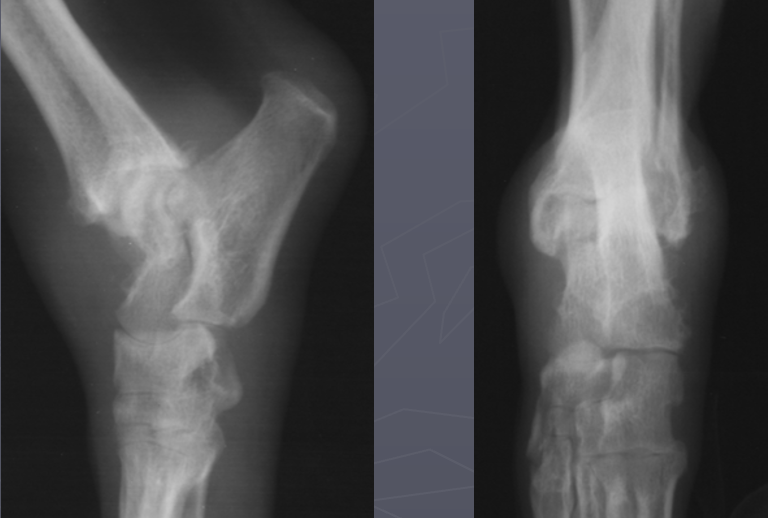

4

What is shown in these radiographs?

moth-eaten lysis